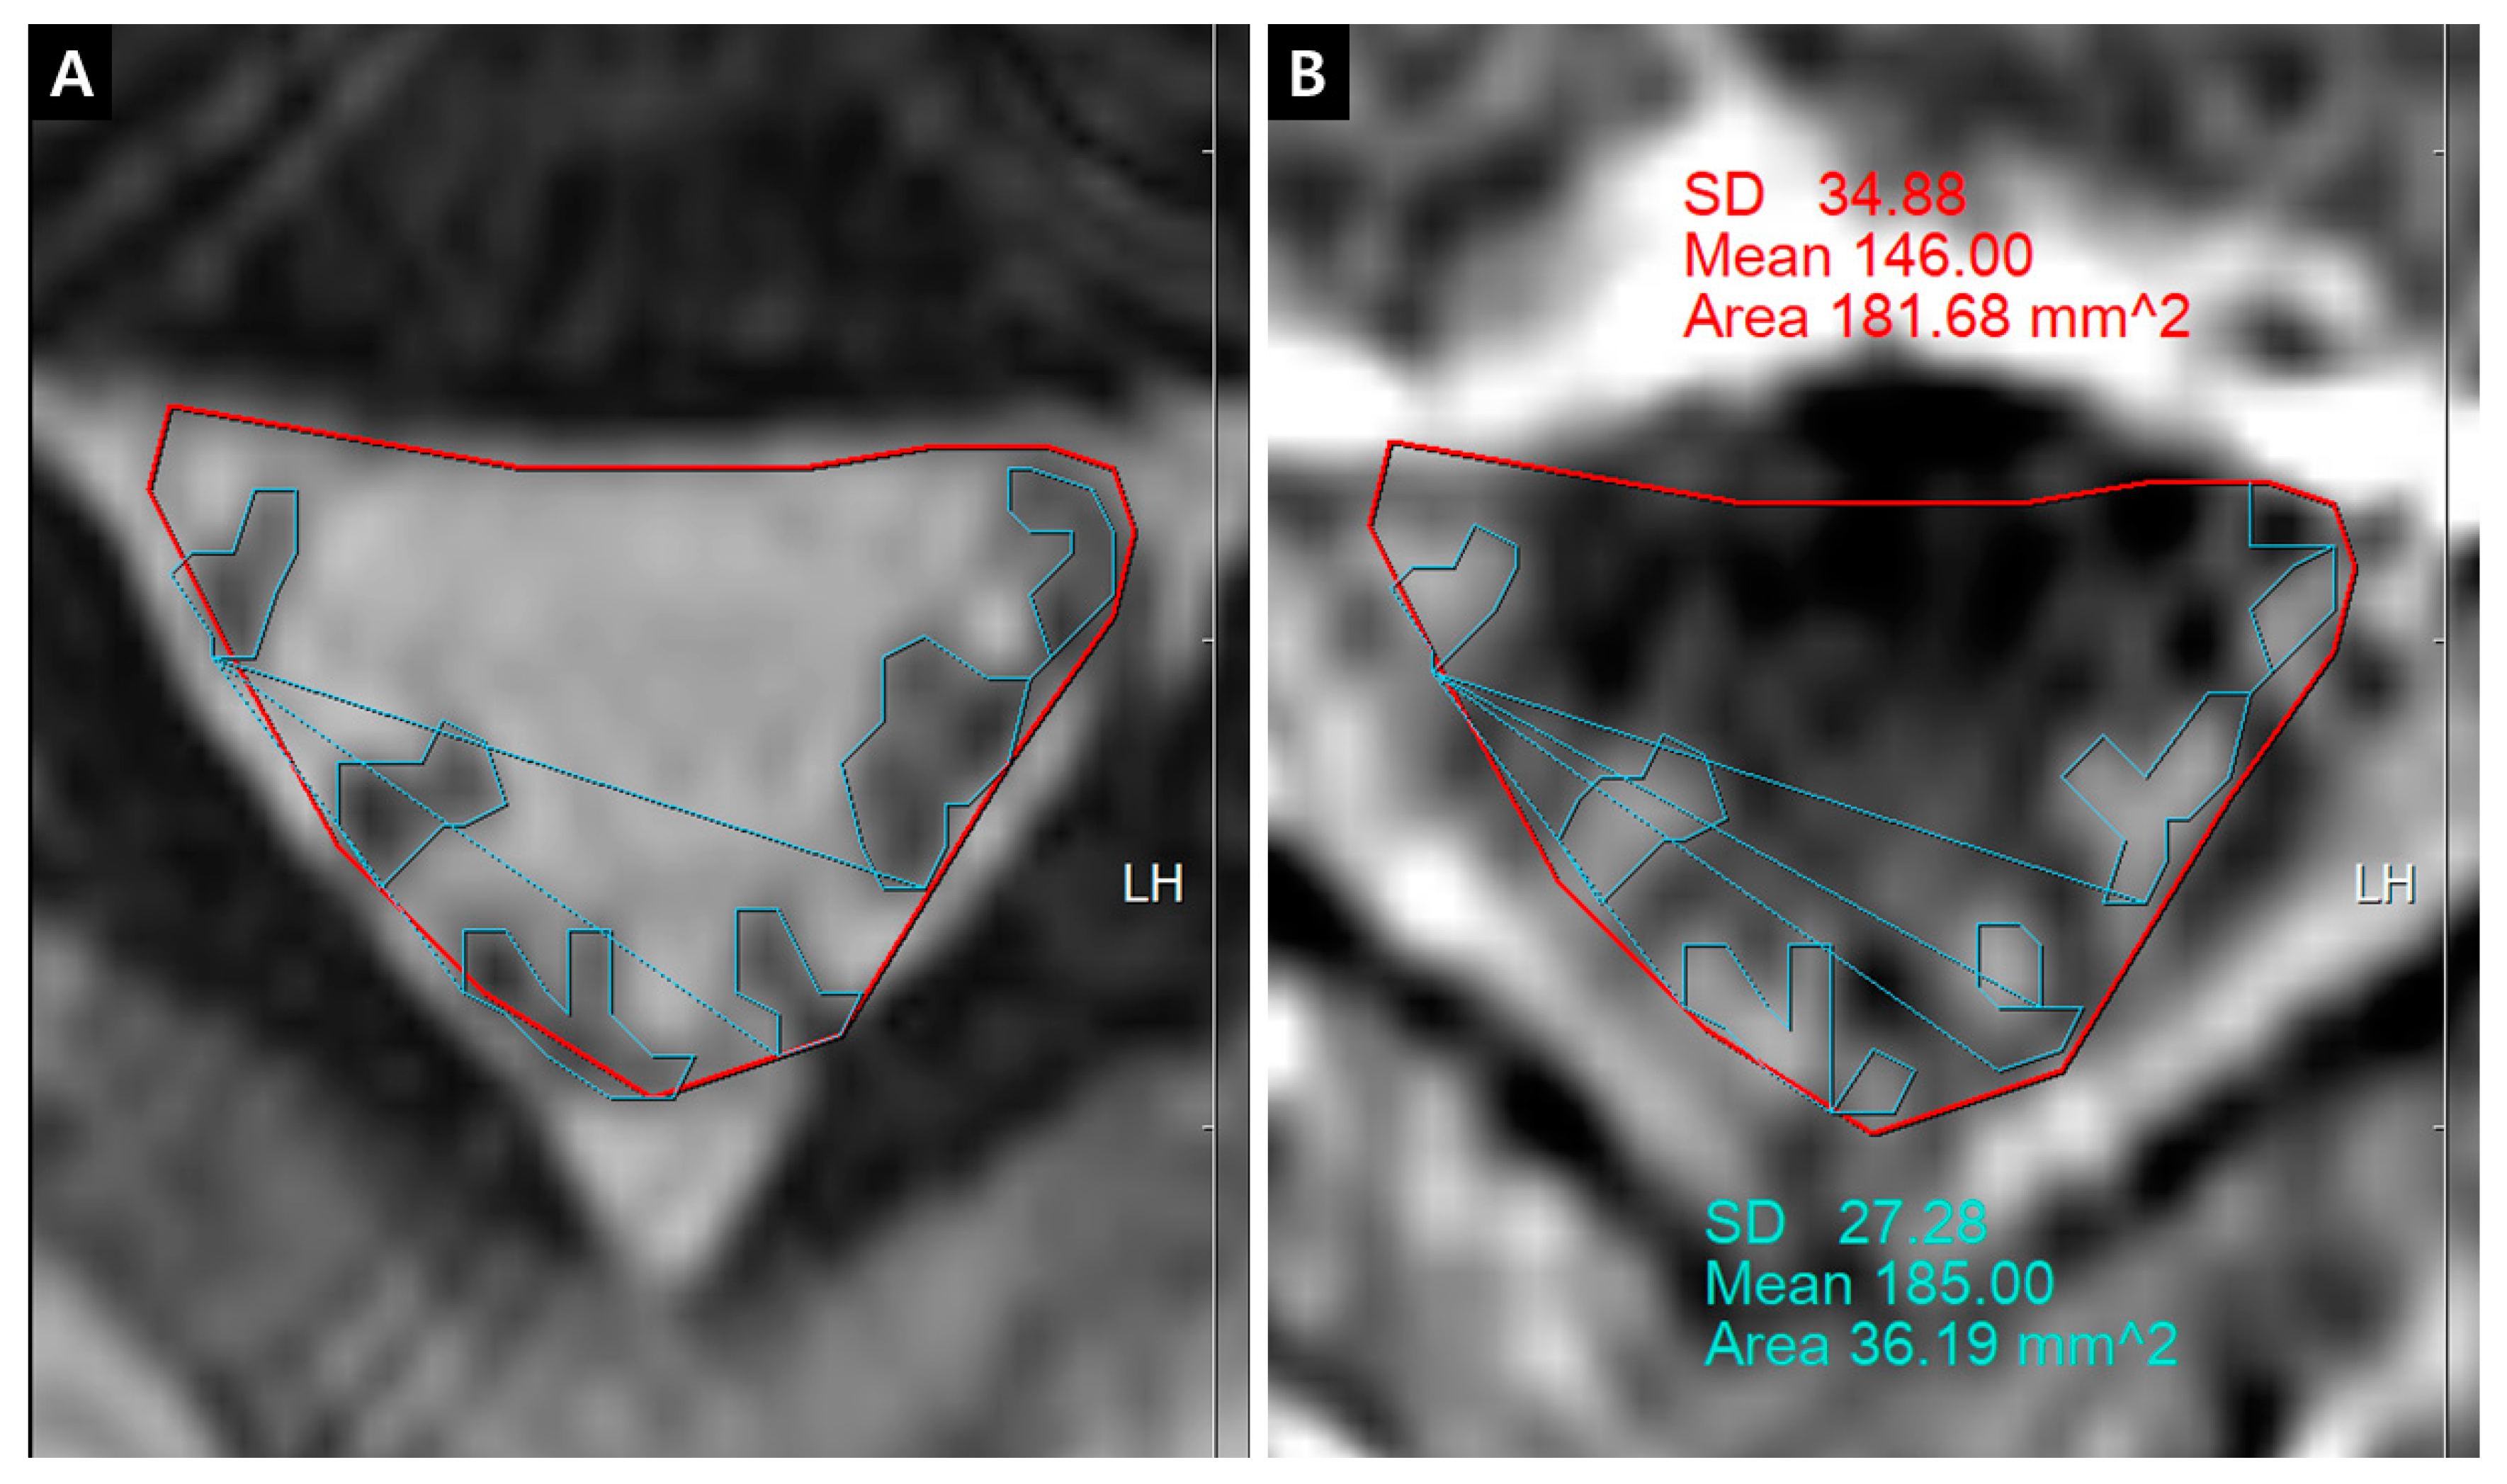

The quantification of IRCE was evaluated by the ratio (%) of signal intensities between the cauda equina and psoas muscle on the same axial enhanced image. The signal intensity of rootlets was measured within the manually defined region of interests (ROIs) along the boundary of the white signal by a digitizer, Maroview software (Infinitt Healthcare Co., Seoul, Korea). To define an exact margin, intrathecal rootlets were marked on the same T2-weighted axial image. The adjustment of the gray scale (window level) was necessary for the discrimination between the rootlets and cerebrospinal fluid. Manual ROI analysis was performed by superimposing previously acquired ROI on the enhanced fat-suppressed T1-weighted image (Figure 5). Two methods were composed of whole rootlets IRCE (WR-IRCE) and maximal spot rootlet IRCE (MS-IRCE) at the most stenotic level (Figure 6). WR-IRCE was obtained by recording the mean signal intensities of all outlined intrathecal rootlets. MS-IRCE was defined as the maximum value in circular ROIs (0.18 mm2) among intrathecal rootlets. In some patients, the large radiculomedullary veins showed strikingly higher signal intensities (>315) than those of other rootlets. These high signals were excluded in the subsequent measurements. The measurement of WR-IRCE and MS-IRCE on the L3–4 and L4–5 levels, respectively, were also performed in the asymptomatic control group to find a difference between such levels. The signal intensity measurement of the psoas muscle was performed within manually defined ROIs (Psoas1), which were delineated along the margin of the unilateral psoas muscle on the same enhanced axial images. In addition, circular ROIs (33.42 mm2, Psoas2) were designated within the medial portion of the psoas muscle corresponding to a mid to posterior disc space to avoid field inhomogeneity (Figure 7). Using these signal intensities, four rootlet-to-psoas ratios were defined (MS/P1 = MS-IRCE/Psoas1*100, WR/P1 = WR-IRCE/Psoas1*100, MS/P2 = MS-IRCE/Psoas2*100, WR/P2 = WR-IRCE/Psoas2*100). Those parameters were analyzed to identify the best possible candidate to stratify patients with lumbar central stenosis.

Figure 5. Whole rootlets IRCE (WR-IRCE) on L4–5 as a control. (A) T2-weighted axial image; (B) fat-suppressed enhanced T1-weighted axial image. SD—standard deviation